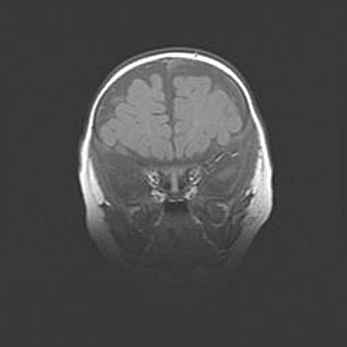

Наружная гидроцефалия с возможной атрофией височных областей.

Возраст: 28 дней

Вес: 3670 г

Пол: мужской

Окружность головы: 38 см

Срок гестации: 40 недель

Гидроцефалия головного мозга у новорожденных – это заболевание, которое характеризуется скоплением избыточного количества спинномозговой жидкости в желудочковой системе головного мозга в результате затруднения её перемещения от места выработки к месту поглощения в кровеносную систему или вследствие нарушения абсорбции. При открытой наружной форме гидроцефалии у новорожденных расширяются и переполняются субарахноидные пространства.

При нормотензивных  формах,  которые,  как  правило,  являются  следствием  перенесенных ишемических  повреждений  паренхимы  мозга,  возможно  сочетание микроцефалии  с нормотензивной гидроцефалией. В основе данных изменений лежит атрофия больших полушарий с преимущественной  локализацией  в  лобно-височных  областях.